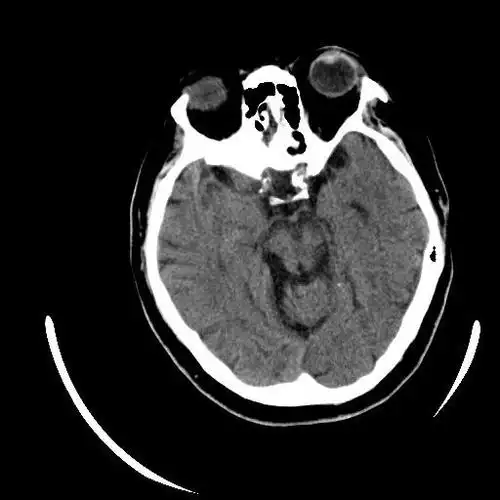

67超急性期大面积脑梗死ct平扫表现

行颅脑ct平扫(可点击图片放大查看)

▎头颅ct平扫有高血压病史10年,最高血压190/100mmhg,目前口服药物